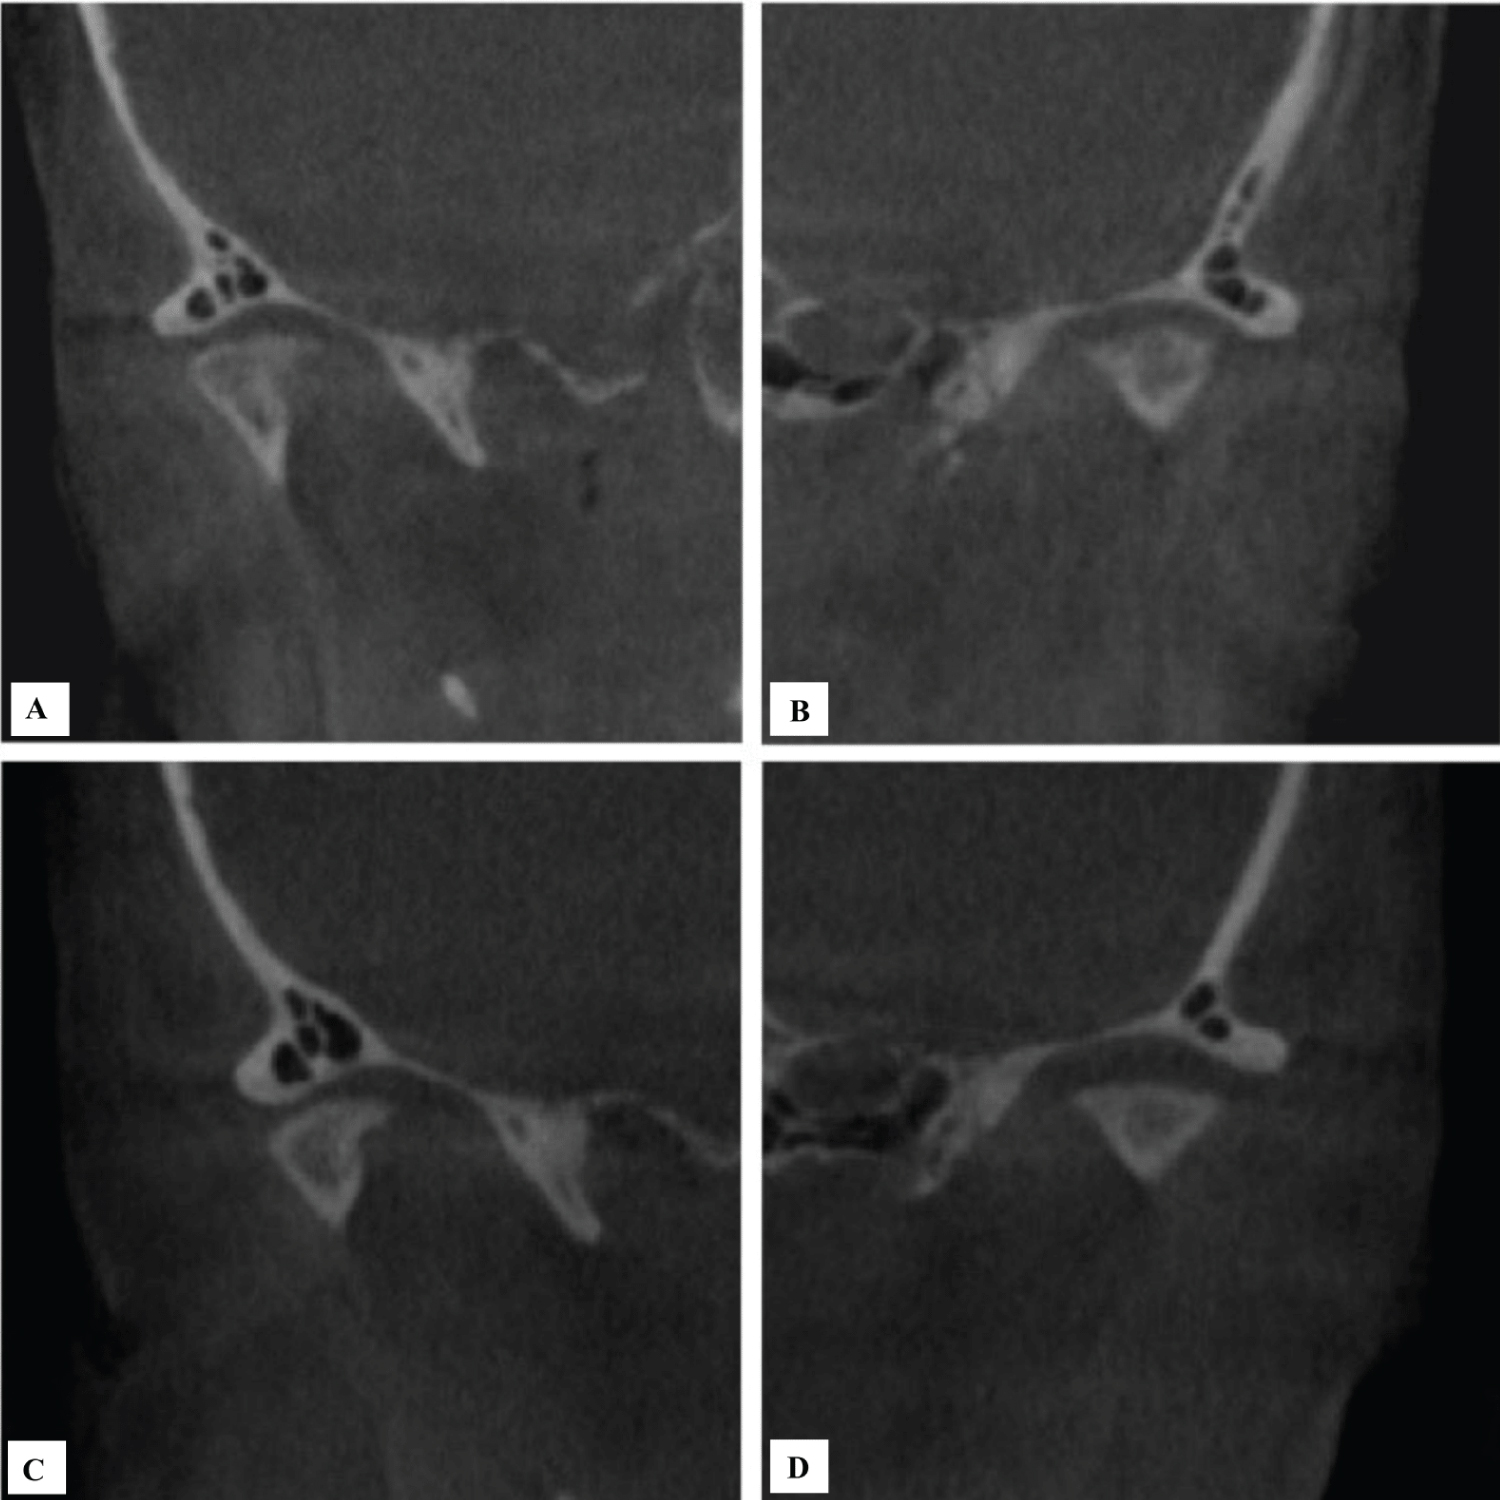

The most significant finding was de novo osseous regeneration along the superior aspects of the condylar heads at approximately 12 months post operatively (Figure 2). However, the two patients who subsequently underwent open joint procedures within six months of arthrocentesis and injection of Procenta, demonstrated bony erosion of the condylar head at the surgical site.

Figure 2: Postoperative computed tomography of the same 63-year-old female patient with left temporomandibular joint degenerative joint disease showing osseous regeneration in the area of condylar head 12 months postoperatively (A) Axial view exhibiting regeneration of bone and recortication of the condylar head; (B) Coronal view again confirming regenerative process at the left condylar head; (C) Coronal view again confirming regenerative process at the left condylar head. View Figure 2